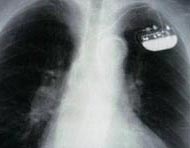

A pacemaker is a small device implanted in the chest. It sends electrical signals to start or regulate a slow heartbeat. It's most often placed in the chest just under the collarbone. A pacemaker may be used if the heart's natural pacemaker (the SA node) is not working correctly, causing a slow heart rate or rhythm, or if the electrical pathways are blocked.

Front view of male chest showing pacemaker.

An implantable cardioverter defibrillator (ICD) looks similar to a pacemaker, though slightly larger. It works very much like a pacemaker. But the ICD can send an energy shock that resets an abnormal heartbeat back to normal.

Front view of male chest showing implantable cardioverter defibrillator.